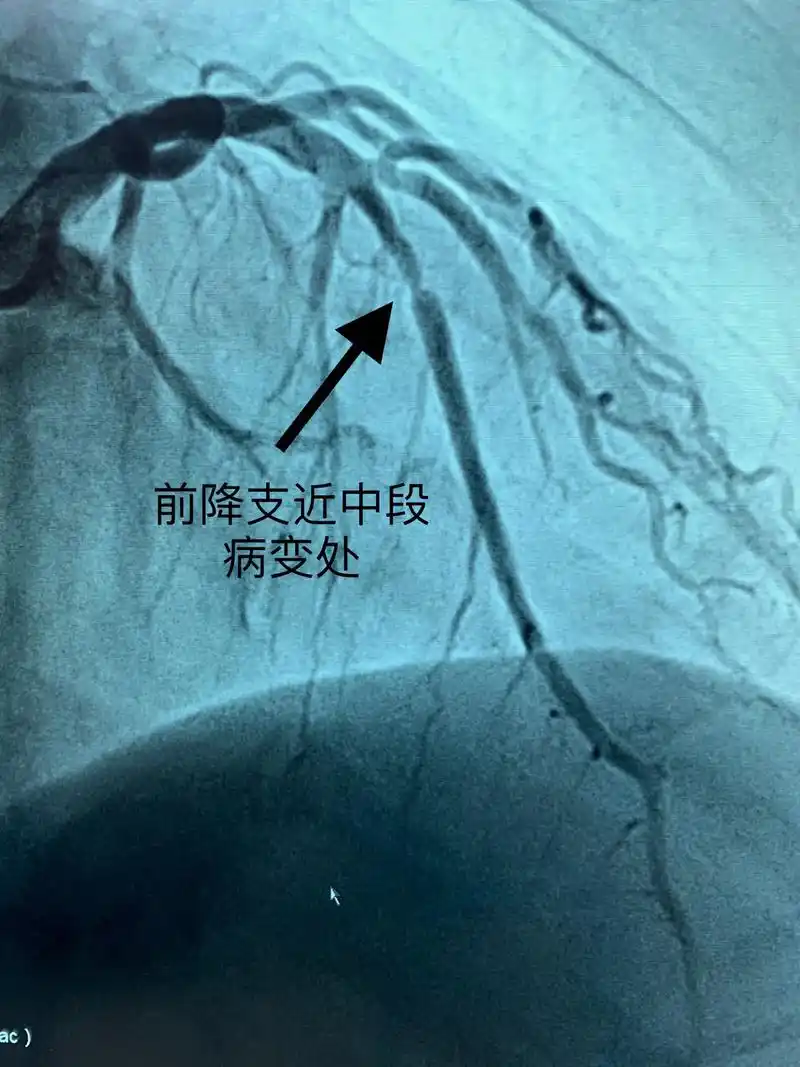

冠脉造影检查是诊断冠心病的金标准,能筛查出不稳定斑块,为你的 - 抖